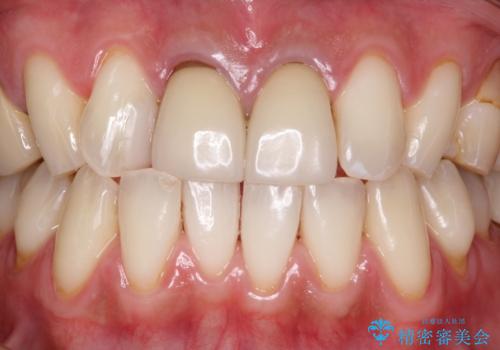

インビザラインでの矯正前にPMTC

- これからインビザラインでの矯正治療が開始する方です。定期的にクリーニングを行っていきたいとのことでした。PMTC30分コースを行いました。

プラーク(細菌の塊)や歯石がたまると歯の表面はザラつきいてきます。そのザラつきは歯周病や虫歯菌の棲家となります。そのまま放置すると、歯肉が腫れてきたり、歯肉から出血したり、口臭が強くでたりします。とくに歯肉の境目は、歯磨きで汚れを除去することが難しく、プラーク(細菌の塊)や歯石が溜まりやすい場所です。

歯並が、がたついている場合はなおさら汚れが溜まりやすいです。矯正治療前や矯正中、定期的にPMTCをすることで、矯正治療中の歯肉トラブルを防ぐことにつながります。